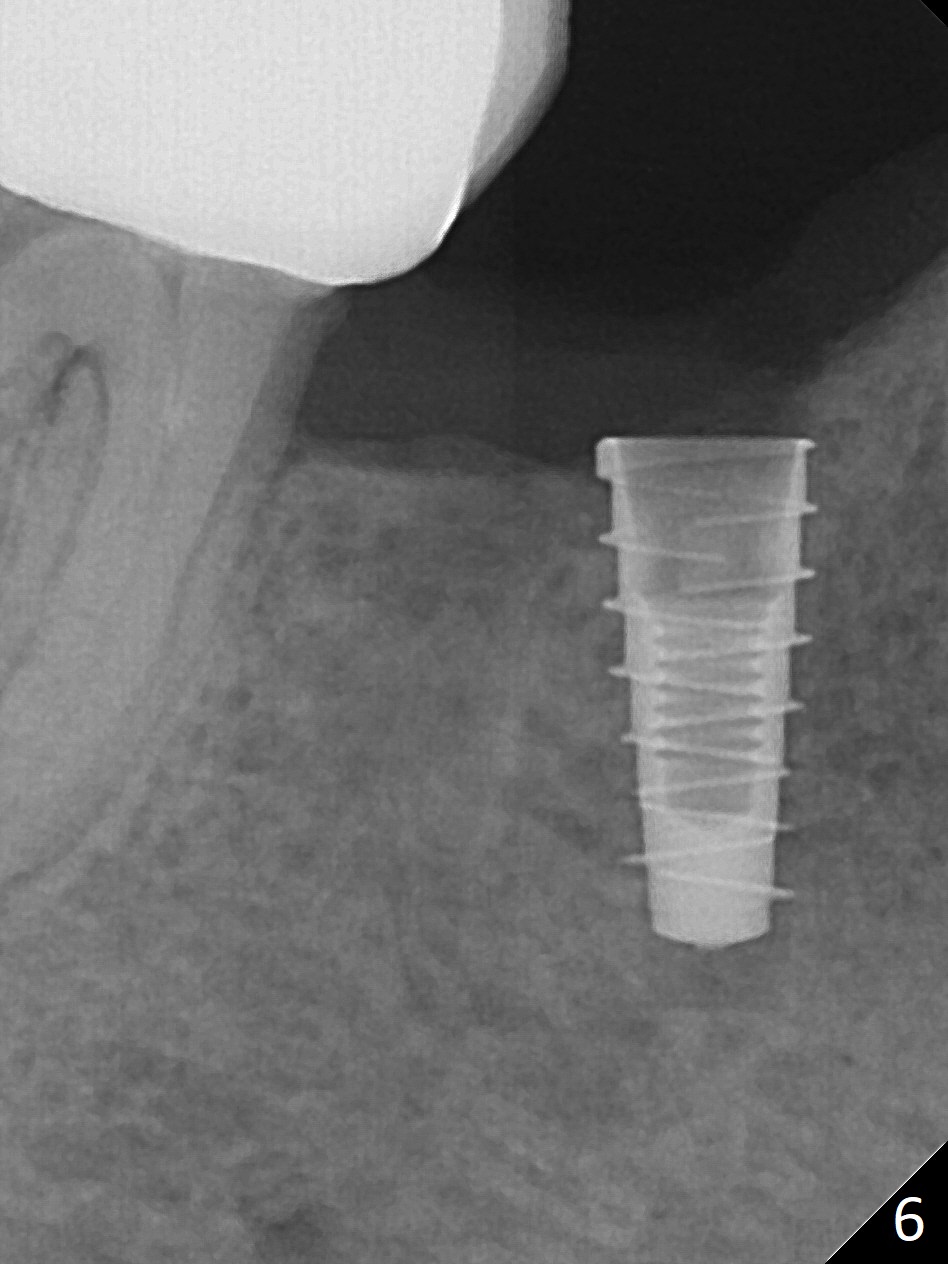

The patient returns for implant placement 11 months post extraction of #28 and 29. With flapless manner, initial osteotomy happens to drop into the original socket of #28 (Fig.4). After use of 3.3 mm Magic Drill (MD) and Final Drill for 15 mm, a 4x11 mm dummy implant is placed (Fig.5). It appears that the implant is long for the site (red dashed line: Mental Loop). However, a definitive implant (4x9 mm, IBS) has difficulty to reach its depth (Fig.6). After several rounds of untorque and retorque, the implant does not seat completely (Fig.7, implant driver disengagement) with autogenous bone placed distal (>). Retrospectively, a larger MD should have been used (3.8 mm) for complete seating in the dense bone. In fact she is post breast cancer treatment with 50% chance of relapse. The patient returns for follow up 1.5 months postop (Fig.8). The wound has healed. Impression is taken 5 months postop (Fig.9). When the crown is cemented, food impaction is an issue between the implant crown and crown at #30. Since the tooth #30 is mesially tilted with distal open margin and apical infection, the tooth will be extracted. Osteotomy is going to be initiated in the mesial slope of the mesial socket (Fig.9 red line). An implant will be placed more or less in the mesial socket (green box).